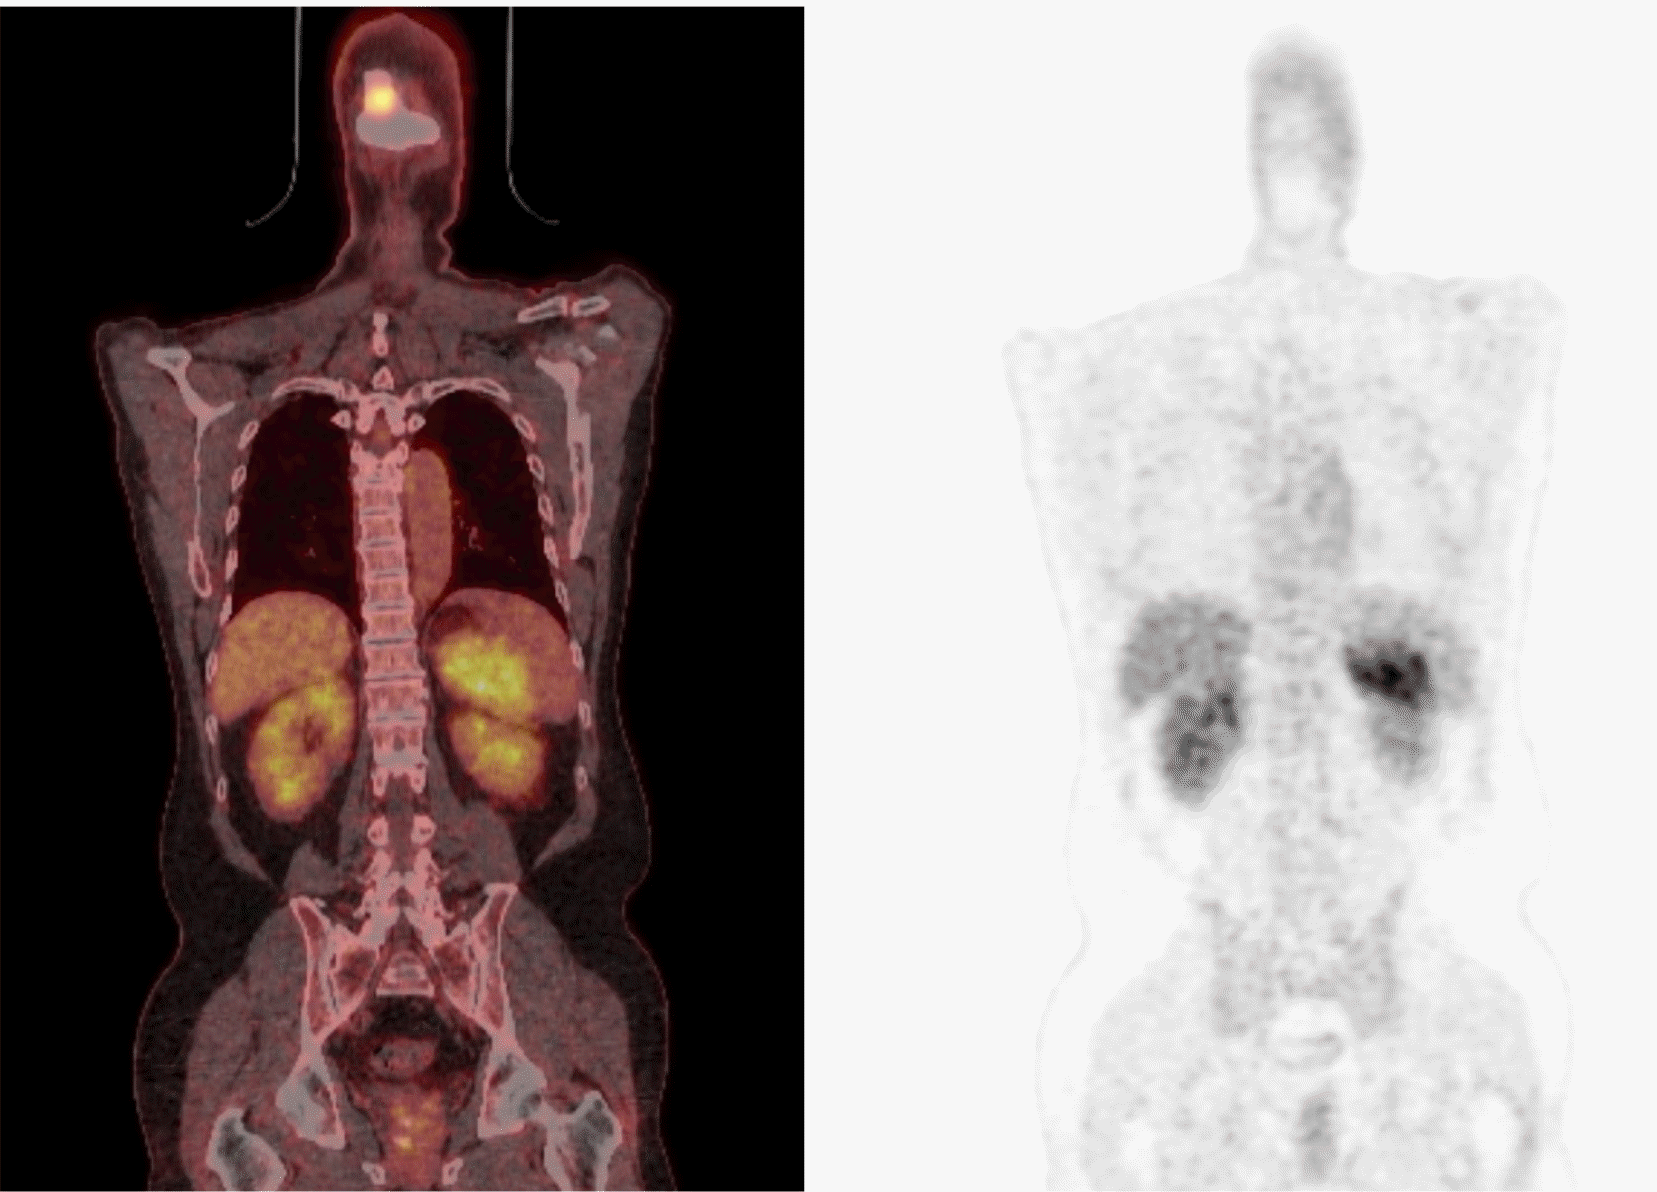

역동적 복부 전산화 단층촬영(Fig. 1A), 그리고 이어서 자기공명영상(Fig. 1B, C) 검사를 시행하였고, 비장 내에 약 6.5 cm 크기의 경계가 뚜렷한 종괴가 관찰되었다. 종괴는 조영증강이 잘 이루어지지 않으며, 내부에 출혈을 동반하고 있었다(Fig. 1A, B). 또한, 경미한 확산 제한을 보였다(Fig. 1C). 추가로 시행한 양전자 방출 단층촬영에서 비장에서 최대 표준 섭취값(Standardized Uptake Value maximum, SUVmax) 9.0으로 측정되는 고대사성 종괴가 관찰되었고(Fig. 2), 그 외 간 및 간외 장기에 특이 소견은 없었다.

Fig. 2

Positron emission tomography-computed tomography (PET-CT) findings. Fluorodeoxyglucose PET-CT scans showing high metabolic uptake in the spleen.